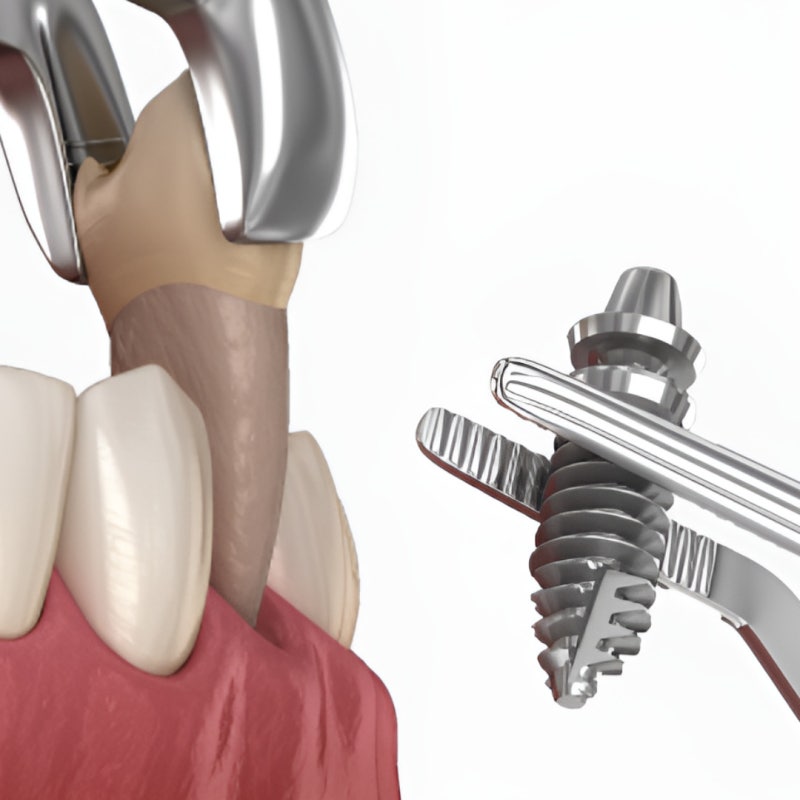

반갑습니다. 치의학 박사 장영준입니다. “임플란트가 필요하다고 하는데.. 솔직히 아플까 봐 두려워요.” 안산 고잔동 치과를 찾으며 이 글을 읽고 계신 분들 중에는 위와 같은 걱정으로, 꼭 임플란트가 아니어도 치료